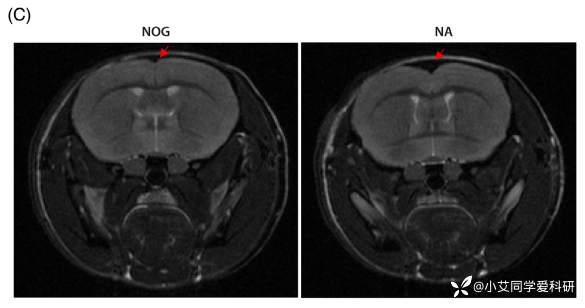

MRI 扫描显示 12 月龄 NA 小鼠皮质体积减少、脑室扩张;